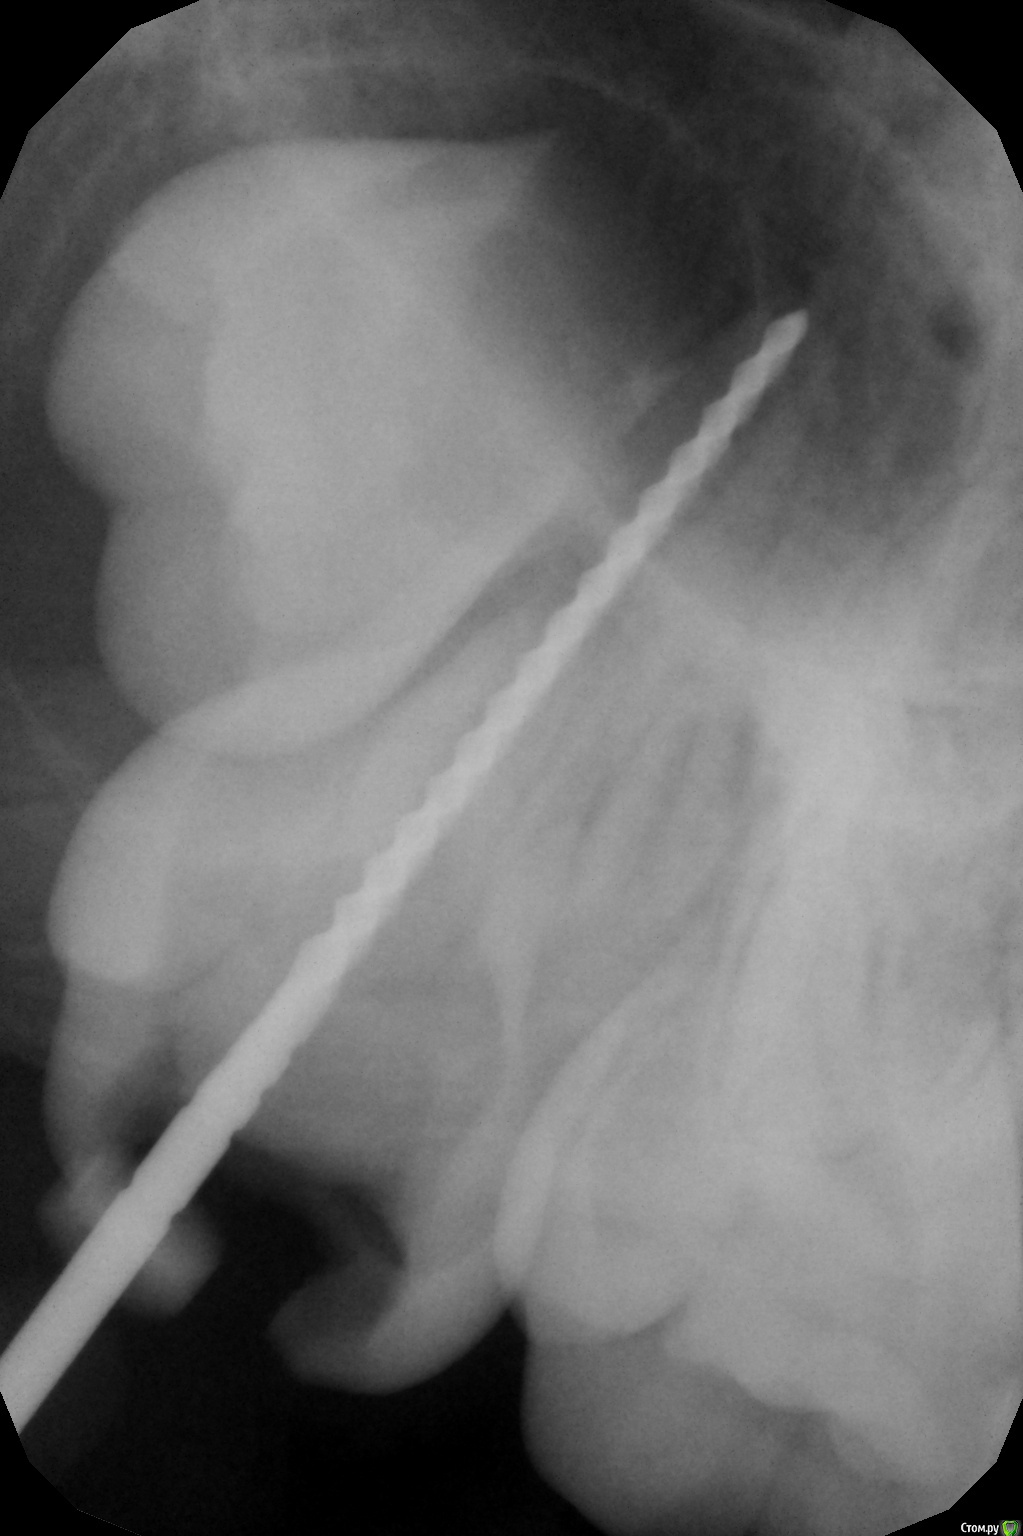

crown Опубликовано 7 мая, 2016 Автор Поделиться Опубликовано 7 мая, 2016 (изменено) Девочка, 14 лет. Диффузный пульпит 17. В щечных получилось создать упор на 40 файле. В небном 70 проваливается за апекс. Запломбировал метапексом, правда без коффера, были сложности с наложением и доступом. Закроется верхушка или нет? Изменено 7 мая, 2016 пользователем crown Ссылка на комментарий

Джима Опубликовано 7 мая, 2016 Поделиться Опубликовано 7 мая, 2016 Закроется, наверно. Только, возможно, придётся добавлять метапекс через время.чего мта апекс не сделали? прямой канал, широкий..чего не удалили вообще ? не рассматривали такой вариант? Ссылка на комментарий

crown Опубликовано 8 мая, 2016 Автор Поделиться Опубликовано 8 мая, 2016 Так как корни не сформированы решил в эту тему закинуть. От удаления отказались, там еще одна такая нижняя семерка. МТА даже не пытался, доступ не удобный, а сносить пол коронки не хочется, да и без оптики я думаю не получится, все размажу по стенкам, другое дело центральный зуб, там попроще . Ссылка на комментарий